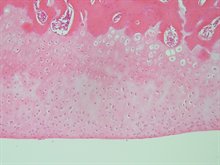

Osteoarthritic knees are more prone to damage following painful inflammatory flares

The topmost concern of people with osteoarthritis (OA) is a reduction in joint pain but the mechanisms of OA pain are complex. People with OA experience “flares” of joint pain. Joint inflammation contributes to OA pain.  We show that OA joints are more sensitive to damage following painful inflammatory flares and the joint damage persists even after the resolution of joint pain. Preventing inflammatory flares may be particularly important in preventing symptoms and long-term joint damage in OA.

For further information, please visit the article